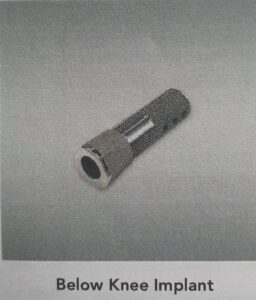

Below knee osseointegration.

The OGAAP-OPL is made up of several different components that can be divided into an internal (endo) module and an external (exo) module. The endo module, a titanium stem, is directly implanted into the bone. There are a range of implants to meet the needs of varying patients.

Osseointegration Prosthetic Limb (OPL) Implant for Lower Leg Amputee